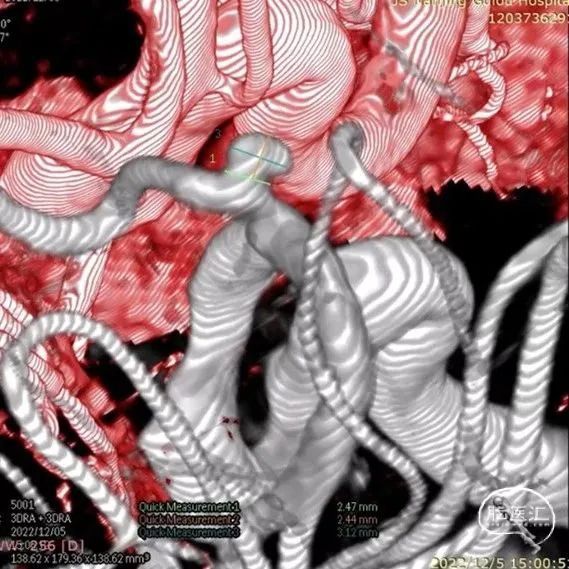

我院头颅CTA:

3D造影

测量

动脉瘤特点解析:动脉瘤位于左侧大脑前动脉A1段起始部,距离颈内动脉分叉处近,指向后方伴子囊,瘤颈约2.92mm,大小约2.59*3.55mm。